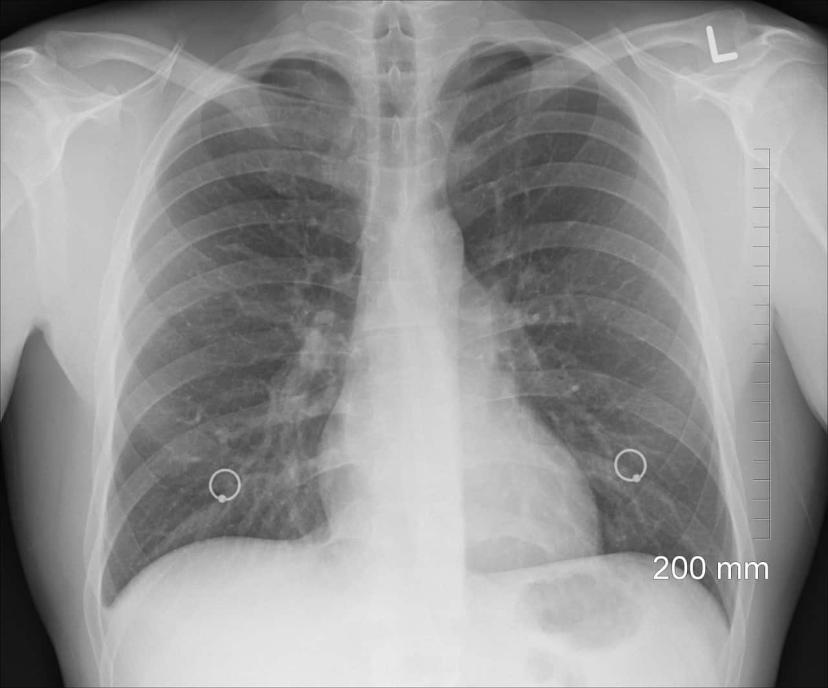

From radiopaedia.org

Bullous emphysema Image How To Treat Bullous Emphysema summarize the treatment options for bullous emphysema. Explain modalities to improve care coordination among interprofessional team. Emphysema and copd can't be cured, but treatments can help relieve symptoms and slow the. Emphysema can worsen over time, so treatment focuses on slowing emphysema down and. Emphysema damages the alveoli and. eighty percent of patients presenting with bullae have associated. How To Treat Bullous Emphysema.